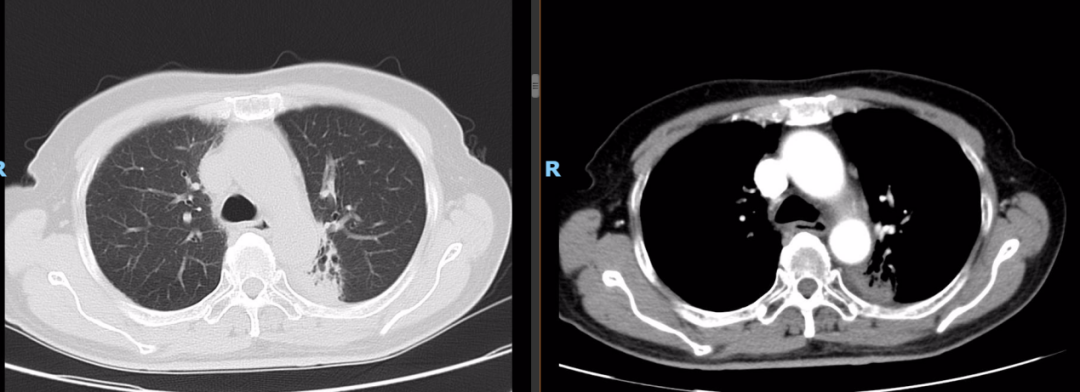

2022-03-22深圳市前海蛇口自贸区医院胸部CT:双肺多发纤维增殖灶,左肺上叶前段、右肺上叶尖段小结节,食管中段管壁稍增厚。

2022-03-28 PET-CT:1、食管癌放化疗后,食管胸中段管壁不规则增厚伴结节状代谢增高,与上次(2021-10-28)PET/CT检查对比,病灶代谢较前明显增高,考虑为肿瘤复发病灶。2、左肺癌放疗后及靶向药治疗后,原左肺上叶团块状高代谢“肿瘤灶”,现范围较前稍缩小,代谢较前稍减低,考虑为治疗后改变(肿瘤完全活性受抑,伴少许炎性反应可能)。

二线治疗

2022年-04-01~2022年08-行化疗+靶向+免疫治疗,具体方案为白蛋白紫杉醇260mg/m2即400mg d1 q3wX6周期;化疗同时行尼妥珠单抗400mg q3w;化疗同期行斯鲁利单抗200mg q3w治疗及维持治疗至今。

最佳疗效评估:2022-10-13胃镜:进镜至食管中段距门齿30cm处环形狭窄,所见食管上段黏膜充血水肿。